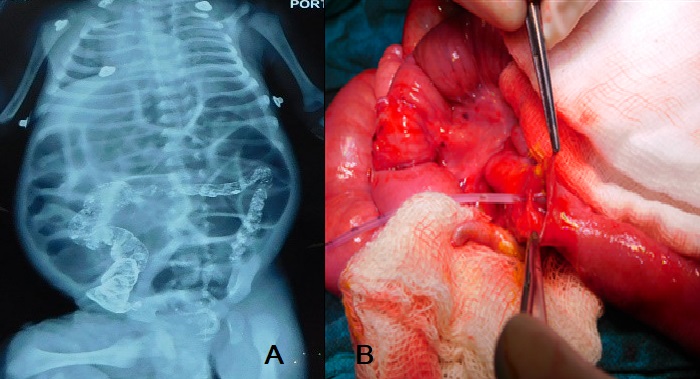

A 12-day-old male neonate presented in the emergency room with constipation for three days and repeated episodes of non-bilious vomiting for one day. The patient had a history of delayed passage of meconium (after 48 hours) at birth. On examination, the abdomen was distended but soft, and bowel sounds present. X-ray abdomen showed multiple air-fluid levels. Suspecting Hirschsprung’s disease, saline enema was started. The patient started passing the stool and the abdominal distension settled down, thus feeding was resumed. The patient tolerated the feeds and started passing stool without enema. The patient was discharged and followed-up in the outpatient department (OPD). After two weeks, the patient again presented with abdominal distension and constipation. Rectal washout was given but the patient passed small amount of stool and abdominal distension persisted. Contrast enema performed showed narrow lumen of the entire colon, and the contrast could not pass proximal to the ileocecal junction (Fig. 1A).

On exploration, hugely distended small bowel loops were found with collapsed colon. We suspected obstruction at the level of ileocecal junction. Thickening of the ileal wall proximal to obstruction site was also noted. A longitudinal enterotomy performed at ileocecal junction revealed a mucosal web at the ileocecal junction with central perforation (Fig. 1B). The web was excised and enterotomy closed transversely. Proximal diversion as ileostomy was given. Immediate postoperative recovery was uneventful, but the patient developed signs of sepsis on 5th postoperative day (sluggish movement of ileostomy, abdominal distention, thrombocytopenia, hypoglycemia, and seizures). Antibiotics upgraded, hypoglycemia corrected, and the patient was put on mechanical ventilation. The patient was weaned off the mechanical ventilation on improvement and discharged after establishing full oral feeding. On follow-up the patient is thriving well; and ileostomy reversal has been planned.

A) Contrast enema showing small caliber colon with non-passage of the contrast beyond the ileocecal region and grossly dilated proximal bowel loops. B) Enterotomy showing web at the ileocecal junction with a central perforation.